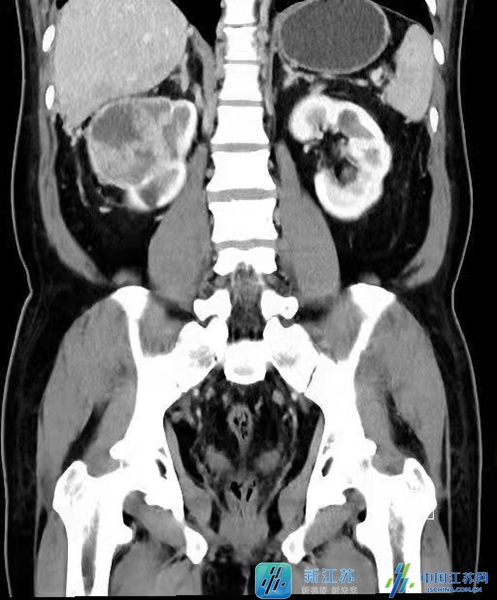

张先生今年58岁,平日里身体一直较为健朗,但在今年9月的一次体检中发现右肾长了一枚肿瘤,这可把张先生急坏了。张先生及家人在多方打听后,慕名来到江苏省人民医院李杰教授门诊就诊。李杰教授在仔细看完他的影像学检查后发现,张先生不仅右肾长了肿瘤,且肿瘤侵入右肾静脉及下腔静脉形成了癌栓,更糟糕的是癌栓上缘已右心房,甚至部分已通过二尖瓣进入右心室,瘤栓一旦脱离,张先生的随时都有生命危险,此时情况非常危险,需要立即入院接受手术治疗。虽然手术风险极大,但是如手术成功,张先生可获得良好的预后。张先生及家人虽然很紧张,但更坚信李杰教授团队的水平和能力,决定立即入院接受手术。

由于张先生的右肾肿瘤巨大,癌栓的位置又已经到达了心房,手术过程中稍有不慎,就会出现心脏骤停以及血管破裂的情况,李杰教授在同心脏大血管外科、麻醉与围术期医学科、手术室、重症医学科、输血科多方共同探讨评估了张先生病情,并与张先生充分沟通后,定下了于开放下行肾癌根治术以及体外循环下右心房、腔静脉癌栓取出术的手术计划。

手术当天,在为张先生麻醉后,先由心脏大血管外科的邵永丰、顾卫东主任团队为其进行体外循环的搭建,为随后李杰教授团队肿瘤及癌栓的取出保驾护航。术中可见张先生右肾肿瘤与肝脏、结肠及周围动静脉粘连严重,手术难度极大。但在李杰教授的仔细又快速的分离下,右肾、右肾动静脉及下腔静脉已完全显露,随后李杰教授先后切断右肾动脉,分离并切断右侧输尿管。至此手术进入了最凶险的癌栓取出过程,李杰教授与顾卫东教授沟通后,随即阻断了远端下腔静脉、左肾静脉、肝十二指肠韧带,开启了体外循环模式,顾卫东教授剪开下腔静脉同时打开右心房,通过二尖瓣将癌栓的一端从右心室完整取出,并细心阻挡防止其脱落,与此同时,李杰教授将右肾完整游离后,沿肾静脉及下腔静脉分离癌栓,在两位教授的通力合作下,确保没有癌栓残留后,完整取出右肾及癌栓并在病人心率、血压都平稳后,恢复了患者的自主血液循环。在经过4个小时的奋战后,病人的肿瘤及癌栓终于全部被取出,手术全程病人的情况较为稳定,所有参与手术人员都是松了一口气。

李杰教授介绍指出:伴有下腔静脉癌栓的肾癌根治加癌栓取出手术是泌尿外科难度最高的手术之一,根据国外报告,围手术期的死亡率为10%。根据美国梅约医学中心的分类法,可将癌栓分为以下五级:0级:癌栓局限于肾静脉内;I级:癌栓侵入下腔静脉内,癌栓顶端距肾静脉开口处≤2cm;II级:癌栓侵入下腔静脉内,距肾静脉开口处>2cm;III级:癌栓生长达肝内下腔静脉水平,膈肌以下;IV级:癌栓侵入膈肌以上下腔静脉内。癌栓级数越高,手术的风险与难度就越大。然而多数情况下,病人无法靠感觉来察觉到肿瘤以及癌栓,因此每年定期做一次全面体检是非常重要的。